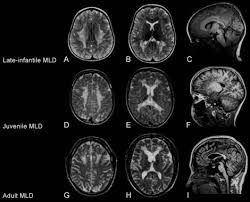

Metachromatic leukodystrophy is a rare hereditary (genetic) disorder that causes fatty substances (lipids) to build up in cells, particularly in the brain, spinal cord and peripheral nerves. This buildup is caused by a deficiency of an enzyme that helps break down lipids called sulfatides.